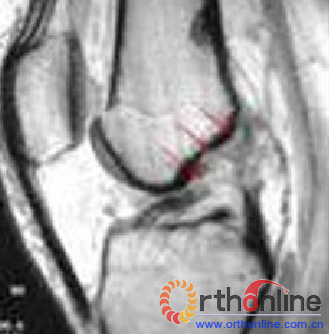

3.影像学表现:核磁共振成像(MRI)因其有高对比度、高分辨率、无创伤性和多切面成像等优点,成为膝关节交叉韧带损伤诊断的最理想的检查方法(。MRI不仅可清楚显示ACL正常形态,还可显示损伤ACL撕裂部位、范围及合并骨折、半月板撕裂及侧副韧带损伤等情况。

图4-4 前交叉韧带损伤MRI